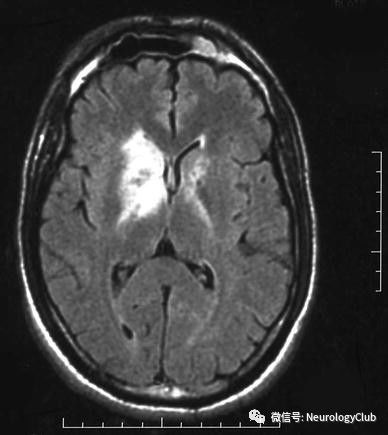

(图6:FLAIR可见右侧基底节和深部白质较大病灶)